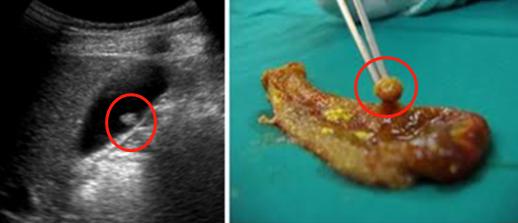

胆囊息肉:多为良性

胆囊息肉很常见,有研究显示,健康体检中胆囊息肉的检出率为0.3%-9.5%。

3.手术指征

约65%以上的胆囊息肉都是良性的非肿瘤性息肉,癌变的发生率在1%-10%之间。

目前,对于出现以下情况的,建议尽快手术治疗。

年龄>50岁;

单发息肉;

伴有结石;

生长时间<3年;

息肉直径>5mm,且患者有手术意愿;

单发息肉直径>10mm,且进行性增大。